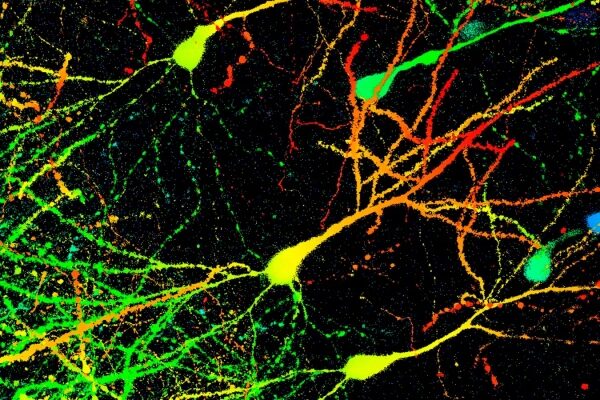

Болезнь Паркинсона возникает, когда происходит истощение нервных клеток в головном мозге. На этом микроснимке показаны нейроны мыши, помеченные флуоресцентным белком для различения клеток на разной глубине. Д-р Гопал Мурти/Научная фотобиблиотека